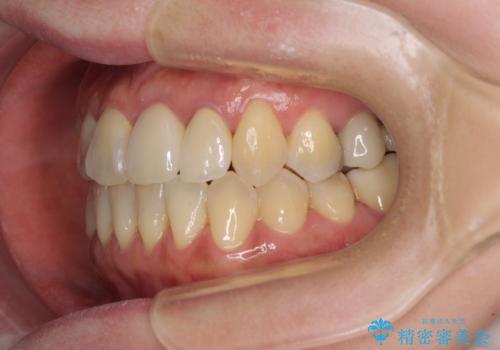

- 前歯の反対咬合により、日々強い痛みを感じているとのことで来院された患者様です。

骨格的に下顎が前方位にありますが、歯列矯正で前歯の被蓋関係を改善することができると判断されたため、インビザラインにより矯正治療を行うこととしました。

前歯が内側に倒れ込む力がかかり、正常な歯ぎしりもできないため、非常に負担のかかりやすい咬み合わせでした。

矯正治療中に上顎前歯が下顎前歯を乗り越える際は、前歯でしか咬めない状況が続くため、食事など不便を感じましたが、治療後には前歯の痛みもなくなり、安定した咬み合わせとなりました。